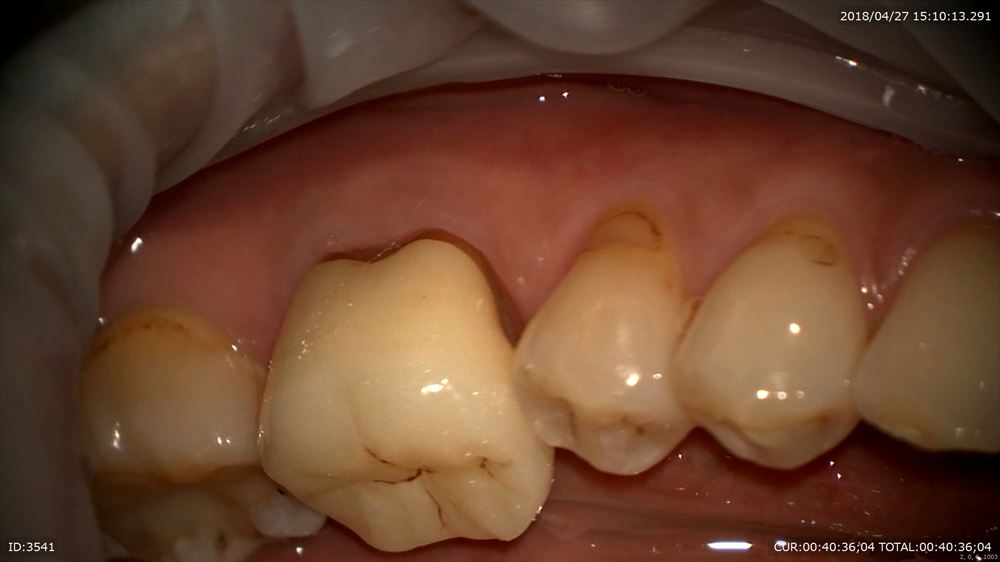

精密な型を採ったので完璧なフィッティング技工士間中先生の腕。いつも大変お世話になっております。

フィット

これならプラーク付かない!

かみ合わせ調整後。

この様に当院では奥歯にも妥協しない治療を致します。